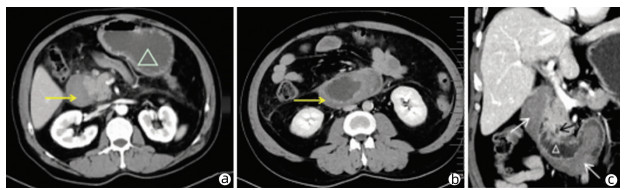

Heterotopic pancreas of the duodenum misdiagnosed as intraperitoneal tumor: A report of three cases

Xing LYU, Jianpeng ZHOU, Kai KOU, Xiaodong SUN, Guoyue LYU

2022, 38(3): 643-645. DOI: 10.3969/j.issn.1001-5256.2022.03.030

Abstract(760) HTML (351) PDF (3871KB)(58)

Abstract: